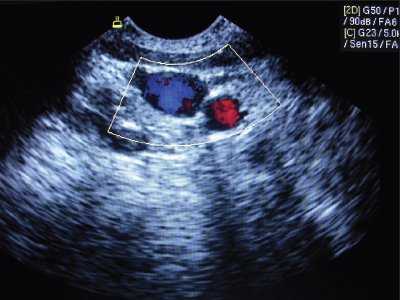

Рис. 2. Нормальное расположение и размеры внутренней яремной вены и сонной артерии при исследовании в поперечном сечении.

Так, в 3% наблюдений нам удалось выявить различные аномалии размеров и расположения сосудов шеи, при наличии которых успешные пункция и катетеризация внутренней яремной вены практически были невозможными. Аномалии условно были разделены на аномалии размеров и расположения сосудов. В норме внутренняя яремная вена находится более поверхностно и латерально по отношению к сонной артерии (см. рис. 2).